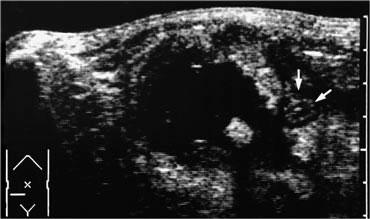

Nếu bên cạnh ruột thừa viêm phát hiện một ổ dịch, đây là dấu hiệu gợi ý áp xe ruột thừa.

Ổ dịch thường chứa khí và được bao quanh bởi mô tăng âm, không thể đè xẹp đại diện cho mạc nối và mạc treo, cũng như các quai ruột lân cận bị dày thứ phát, đang cố gắng bịt kín áp xe khỏi khoang phúc mạc.

Nếu phát hiện áp xe ruột thừa và không có viêm phúc mạc rõ ràng, dẫn lưu qua da là phương pháp điều trị được lựa chọn.

Ở những bệnh nhân ổn định không sốt và chỉ đau nhẹ, thậm chí có thể khôn ngoan khi chờ đợi áp xe tự dẫn lưu vào quai ruột lân cận.

Bên trái là hình ảnh ổ áp xe chứa sỏi phân.

Lưu ý ruột thừa viêm (mũi tên) nằm cạnh ổ áp xe.